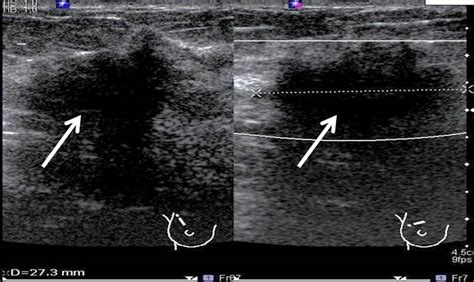

Delving deeper into the implications of having an unspecified site for recurrent female breast cancer in the right breast , and how ICD-10 codes handle this, we see how crucial even these less detailed codes are. Sometimes, clinical documentation might not pinpoint the exact quadrant or location within the breast where the recurrence has appeared. This can happen for various reasons – perhaps the recurrence is diffuse, or initial imaging shows suspicious areas that haven’t yet been biopsied to confirm the precise origin. In these instances, coders must rely on the most general code available that still accurately reflects the known information: that the cancer is recurrent , it’s in the right breast , and its specific location within the breast is unspecified . This typically means using a code that denotes ‘malignant neoplasm of breast, unspecified site’ but is further qualified by the laterality (right breast) and the context of recurrence. The ICD-10-CM system provides codes such as C50.91, ‘Malignant neoplasm of unspecified site of female breast, right breast,’ to capture this. However, the critical part is ensuring that the documentation explicitly states ‘recurrence.’ Without this clear indication, a coder might miss the nuance, and the record might not reflect the patient’s history accurately. The ability to code for ‘unspecified site’ recurrence is not a flaw in the system; rather, it’s a recognition of the realities of clinical practice. It allows for the documentation of a significant event – the return of cancer – even when all pathological or radiological details aren’t immediately available. This is vital for tracking the disease’s behavior. For example, understanding how often recurrences occur within the breast tissue itself, regardless of the exact spot, compared to metastasizing to lymph nodes or distant organs, is important for treatment planning and research. Recurrent breast cancer management often involves different therapeutic approaches depending on whether it’s local, regional, or distant. By using codes like C50.91 with the understanding that it represents recurrence, we preserve valuable data points. This allows for broader statistical analysis of recurrence patterns within the breast, informing oncologists about potential trends and aiding researchers in identifying factors that might predict such recurrences. Moreover, for patient care continuity, knowing that a recurrence has occurred in the right breast, even if the precise location is pending further investigation, guides immediate clinical decisions. It flags the patient for closer monitoring and potentially different treatment protocols than if it were a new primary tumor. The ICD-10 codes , therefore, serve as a robust, albeit sometimes generalized, descriptor that maintains the integrity of the patient’s medical record and contributes to comprehensive health data. The flexibility in ICD-10 to accommodate unspecified sites acknowledges that medical diagnoses are often a process, and the coding system must adapt to reflect the information available at any given time, ensuring that crucial aspects like recurrence are not lost in the details.